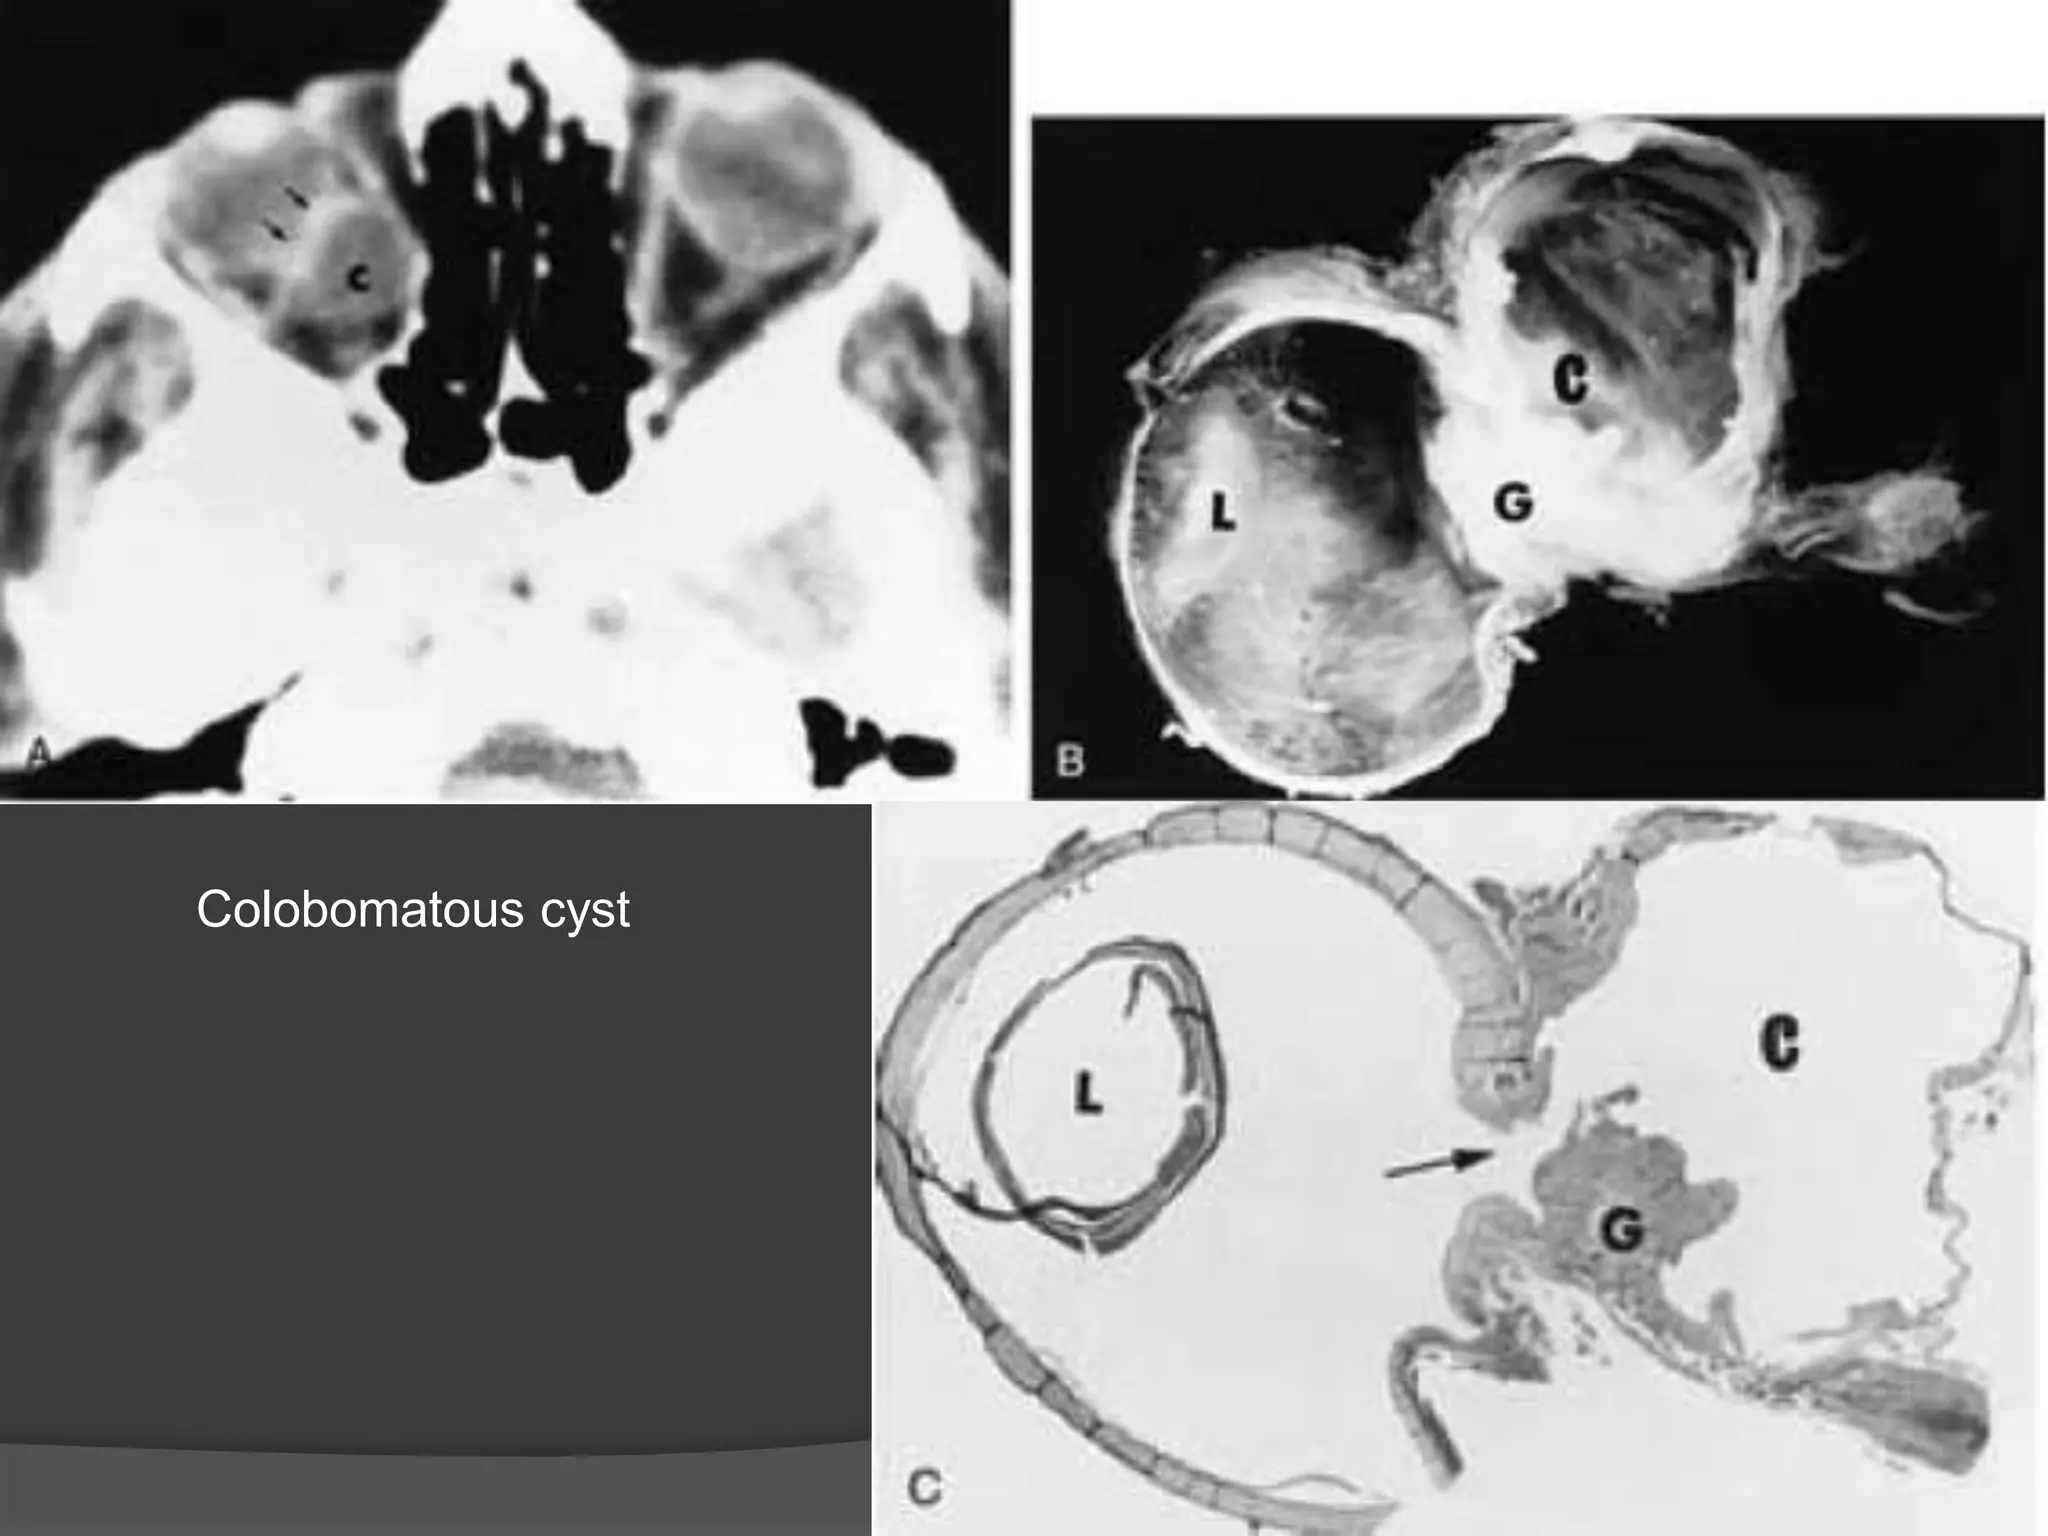

• #8 Colobomatous cyst. A, Axial CT scan shows bilateral microphthalmia and a large cyst (C) separated from the right globe by a band of enhancement (arrows), which is related to abnormal gliotic tissue. B, Anatomic section of an enucleated right eye. Note the small eye, large colobomatous defect, abnormal white tissues, gliotic tissues (G), and large cyst (C). Note the lens (L) and the optic nerve. C, Histologic section of an eye shows a large retinochoroidal coloboma (arrow), gliotic tissue (G ), cyst (C ), and lens (L).

• #9 Colobomatous cyst. Axial CT scan shows microphthalmic eyes with large cysts (arrows).